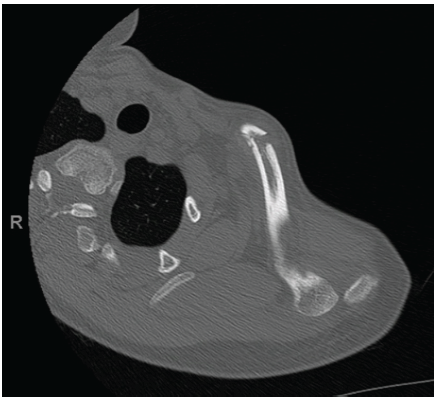

Given the complexity of the injury, a computed tomography (CT) scan with 3D reconstruction was indicated to precisely assess the extent of the clavicle fracture and confirm the posterior dislocation of the distal clavicle. After radiological confirmation of the posterior dislocation (Fig. 3) associated with the medial clavicle fracture, surgical treatment was chosen due to progressive clavicular shortening with altered scapulothoracic biomechanics, risk of chronic clavicular instability, and potential persistent pain caused by clavicular impingement with surrounding muscles and structures, leading to mobility difficulties, particularly in abduction and flexion.

Figure 3: Computed tomography scan with 3D reconstruction, with confirmation of the posterior dislocation of the acromioclavicular joint associated with the medial clavicle fracture.